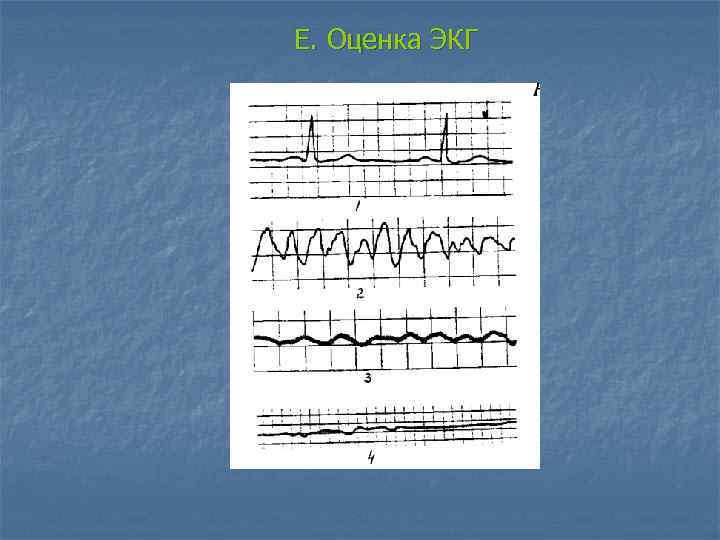

E. Оценка ЭКГ